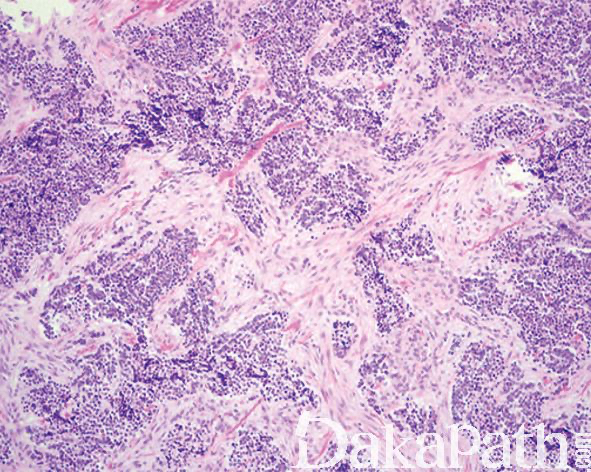

镜下主要可见 2 种细胞,神经母细胞样细胞和上皮性细胞;

神经母细胞样细胞为小的圆形或小立方,核深染、固缩状,多呈巢状或假腺泡状排列;有时该类细胞之间可见神经纤维网样物质;

上皮性细胞体积大,胞质含色素,核呈空泡状,核分裂像罕见,围绕巢状或假腺泡状结构周围;

细胞巢之间可见致密的纤维结缔组织,位于颅面部的肿瘤常可见到骨小梁浸润;